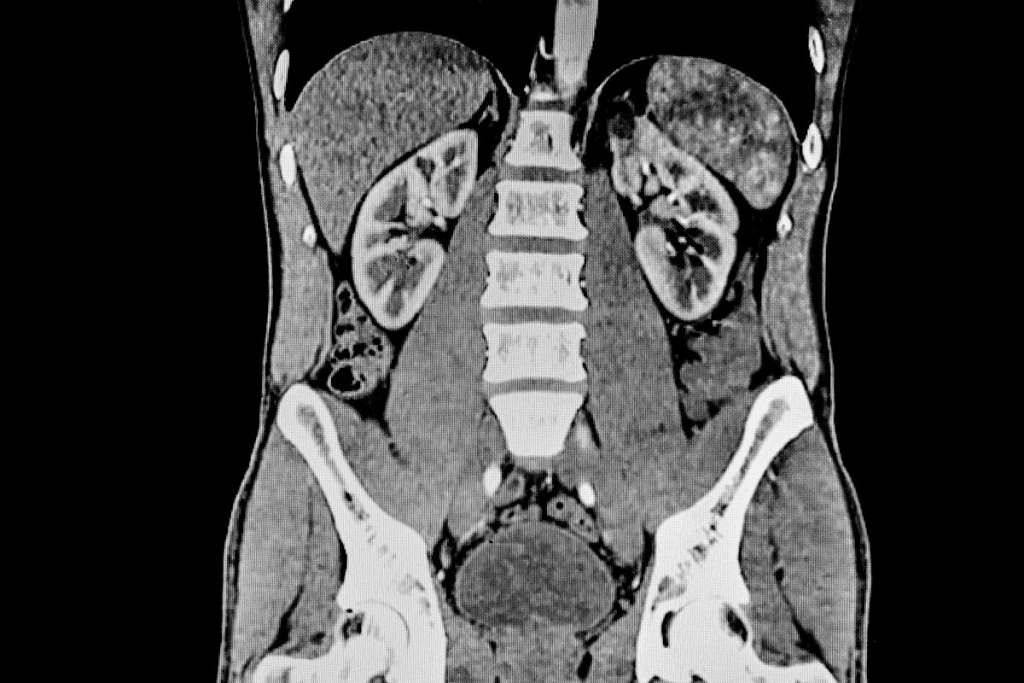

Getting your bladder ready is key for cancer staging and diagnosis with a pelvic MRI. The MRI’s accuracy depends a lot on how full the bladder is. This is very important for spotting muscle-invasive bladder cancer.

Muscle-Invasive Bladder Cancer Evaluation

For muscle-invasive bladder cancer, optimal bladder distention is critical. A well-filled bladder helps see the bladder walls and nearby areas better. This makes for more precise checks.

Diagnostic Accuracy Rates with Proper Bladder Preparation

Research shows that with the right bladder prep, doctors can spot muscle-invasive bladder cancer with high accuracy. They can be over 80% sensitive and 90% specific. This shows how important following prep guidelines is for good results.